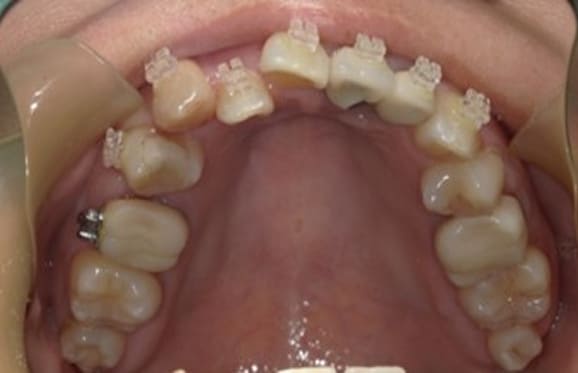

● C4を超え歯根までの虫歯を抜歯、スペースを利用して歯並び全体を整えた症例

藤沢デンタルオフィスの虫歯や破折で抜歯後の部分矯正